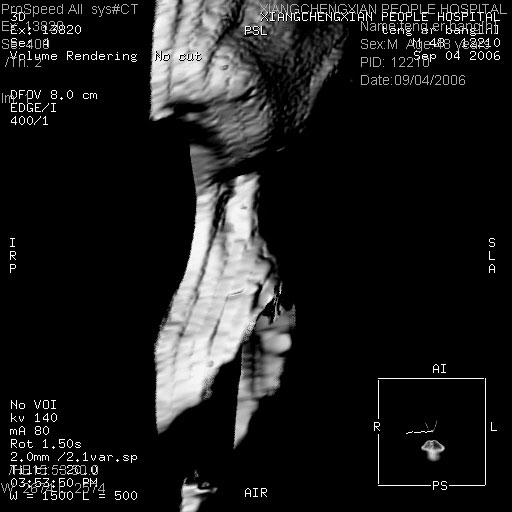

ct:平扫+冠扫:双侧鼻骨对比,冠扫s6#示右侧鼻骨尖部可见线状低密度影,边缘光滑,并见硬化.软组织未见肿胀.

诊断意见:鼻额缝(鼻骨与上颌骨额突缝),但个别同志认为是骨折.因此请同行们会诊.多谢了!